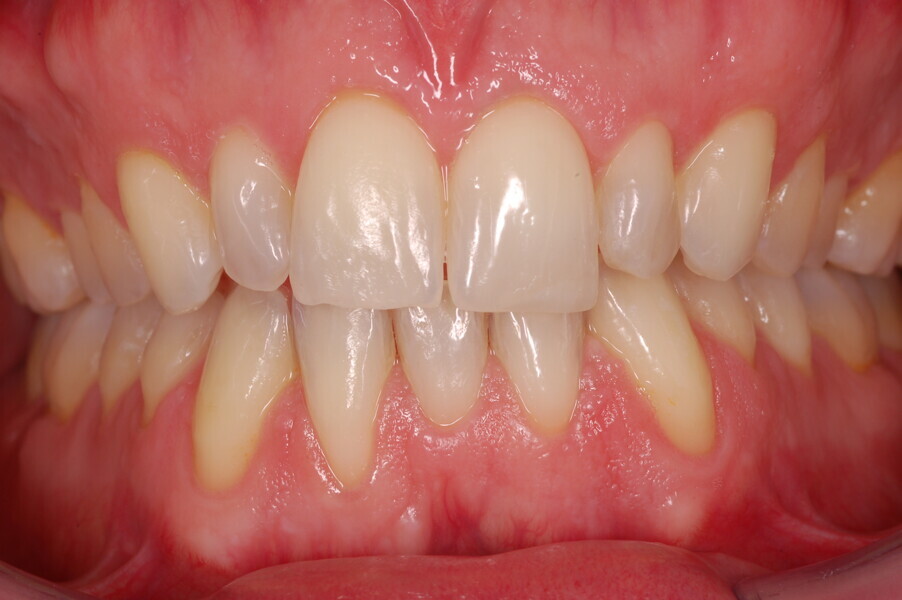

Fig. 45–50: Sequential frontal intra-oral photographs illustrating progressive levelling and alignment and uprighting of the mandibular right lateral incisor.

Fig. 46.

Fig. 47.

Fig. 48.

Fig. 49.

Fig. 50.